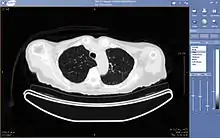

A chest image displayed via a PACS

A full PACS should provide a single point of access for images and their associated data. That is, it should support all digital modalities, in all departments, throughout the enterprise.